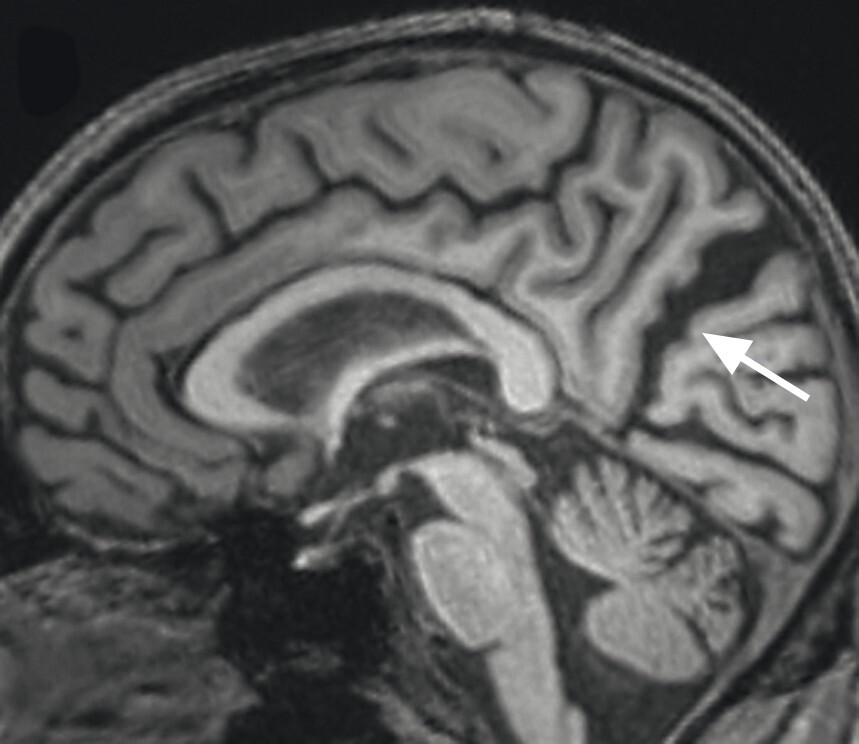

Abb. 69.6 Parkinson-Syndrome: Differenzialdiagnose Demenz mit Lewy-Körperchen.

86-jähriger Patient mit schwerer posturaler Instabilität und Rapid-Eye-Movement-Schlafstörung. Bekannte Hyposmie, Obstipation, keine klassische hypokinetisch-rigide Klinik. Zusätzlich progressive Verschlechterung der kognitiven Fähigkeiten mit speziell visuokonstruktiven Problemen. Im MRT zeigen sich eine grenzwertige Hippokampusatrophie (a, Pfeile) und eine deutliche parietookzipitale Atrophie (b, c). Die deutliche Erweiterung der Pars marginalis des Sulcus cinguli (c, roter Pfeil), des Sulcus parietooccipitalis (c, gelber Pfeil) und des Sulcus calcarinus (c, grüner Pfeil) ist am besten auf T1w 3-D-Sequenzen in axialer und sagittaler Schichtung zu erkennen.

a Koronar reformatierte T1w MRT-Sequenz.

b Axial reformatierte T1w MRT-Sequenz.

c Sagittale T1w MRT-Sequenz.